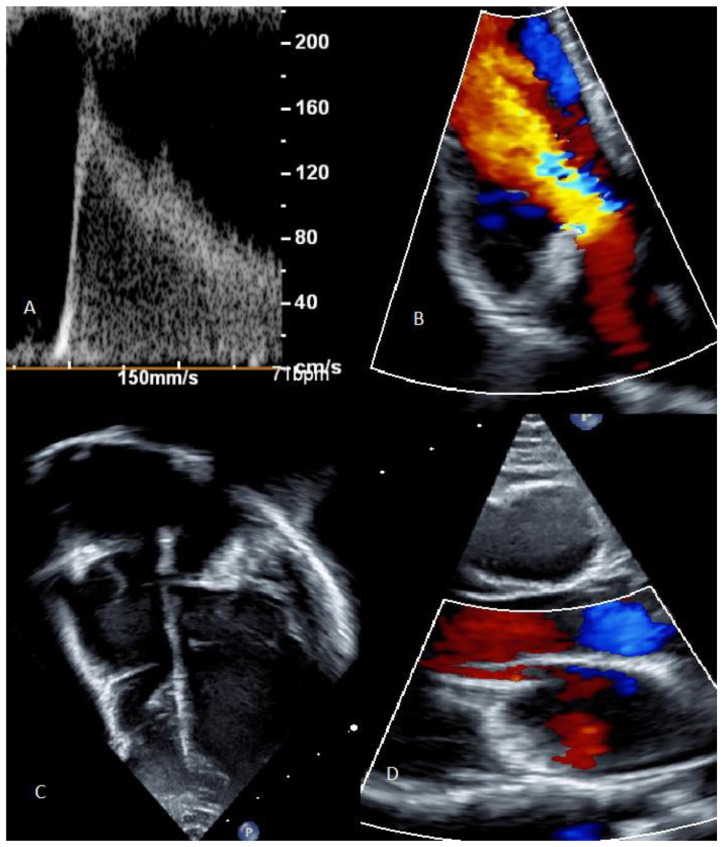

Cardiac strangulation is a rare but potentially lethal complication of epicardial pacemaker insertion. We present the case of a 9-year-old girl who was identified as having cardiac strangulation on routine follow-up for an epicardial pacemaker inserted on day 1 of life for congenital complete heart block (CCHB). The potential clinical presentations and risk factors for pacemaker strangulation are then discussed.